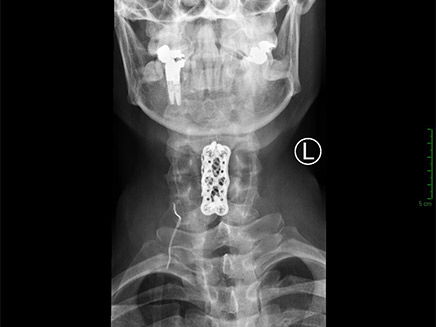

"הייתי צריך לכרות לו באופן מלא חוליה ולהחליף אותה ואת הדיסקים המקיפים אותה בחוליה מלאכותית", תיאר ד"ר אמיתי אמיר, מנהל היחידה לניתוחי עמוד שדרה במחלקה האורתופדית, בשיחה עם 'מאקו'. "תוך כדי הניתוח ניטרנו באמצעים מתקדמים את הפעילות העצבית שלו".

באמצע הניתוח זיהה אחד הרופאים שינוי בפעילות העצבית, וקרא: "מזהים תגובות טובות מרגל שמאל". "בשלב הזה אני מבין שהצלחנו", ציין ד"ר אמיר בשיחה עם 'מאקו'. "המטופל חזר יחסית מהר לתפקד כמעט כמו קודם. הרבה פעמים אין תחליף לריצה לחדר ניתוח - העובדה שקצב הטיפול שלנו היה מהיר היא גורם מכריע בהחלמה המהירה והמלאה שלו".